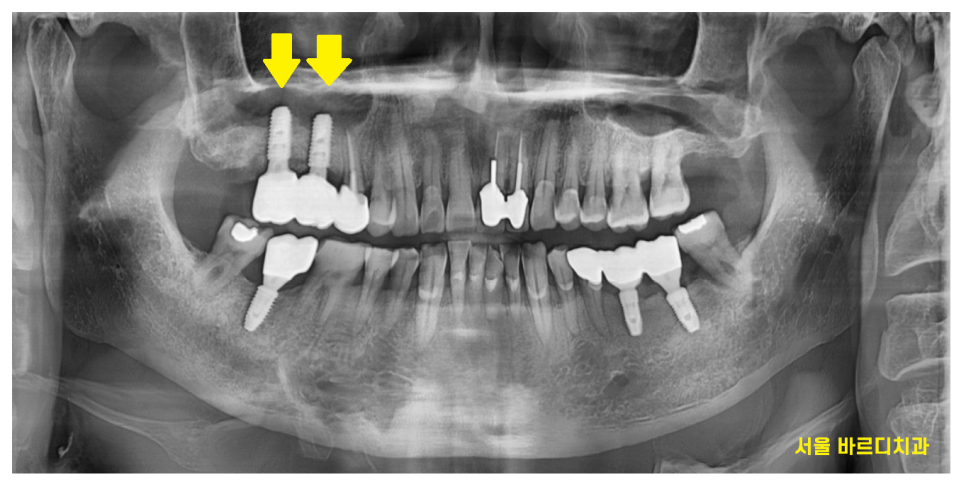

이전 글에서 언급해드렸듯

상악동 거상술이 잘된 임플란트는

돔 형태로 올라간 것을 확인하실 수 있습니다.

오늘의 환자분도

상악동 막이 예쁘게 잘 올라갔네요

24.01.23

일반적으로 윗니 어금니의 경우 4~6개월 정도 기다리지만

감일동 치과에서는 장비를 사용하여

감일동 임플란트와 내 뼈가 단단하게 잘 붙었나 확인합니다.

안정적인 결과가 나오면

오래 기다리지 않고도

바로 씹는 부분인 머리를 만들어드리는데요.